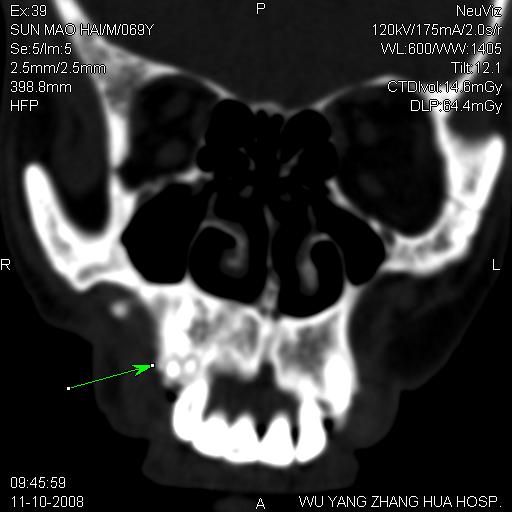

标题: CT16568:右面部瘘管半年余,无其它不适. [打印本页]

标题: CT16568:右面部瘘管半年余,无其它不适.

考虑右上颌异位齿(或斜向阻生齿)并根尖脓肿。

右上颌异位齿(或斜向阻生齿)

1.右上颌异位齿

2.右上颌化脓性骨髓炎

3.右下鼻甲肥大

支持三楼意见。(这种长法还真少见,再长再尖点就成獠牙了。)